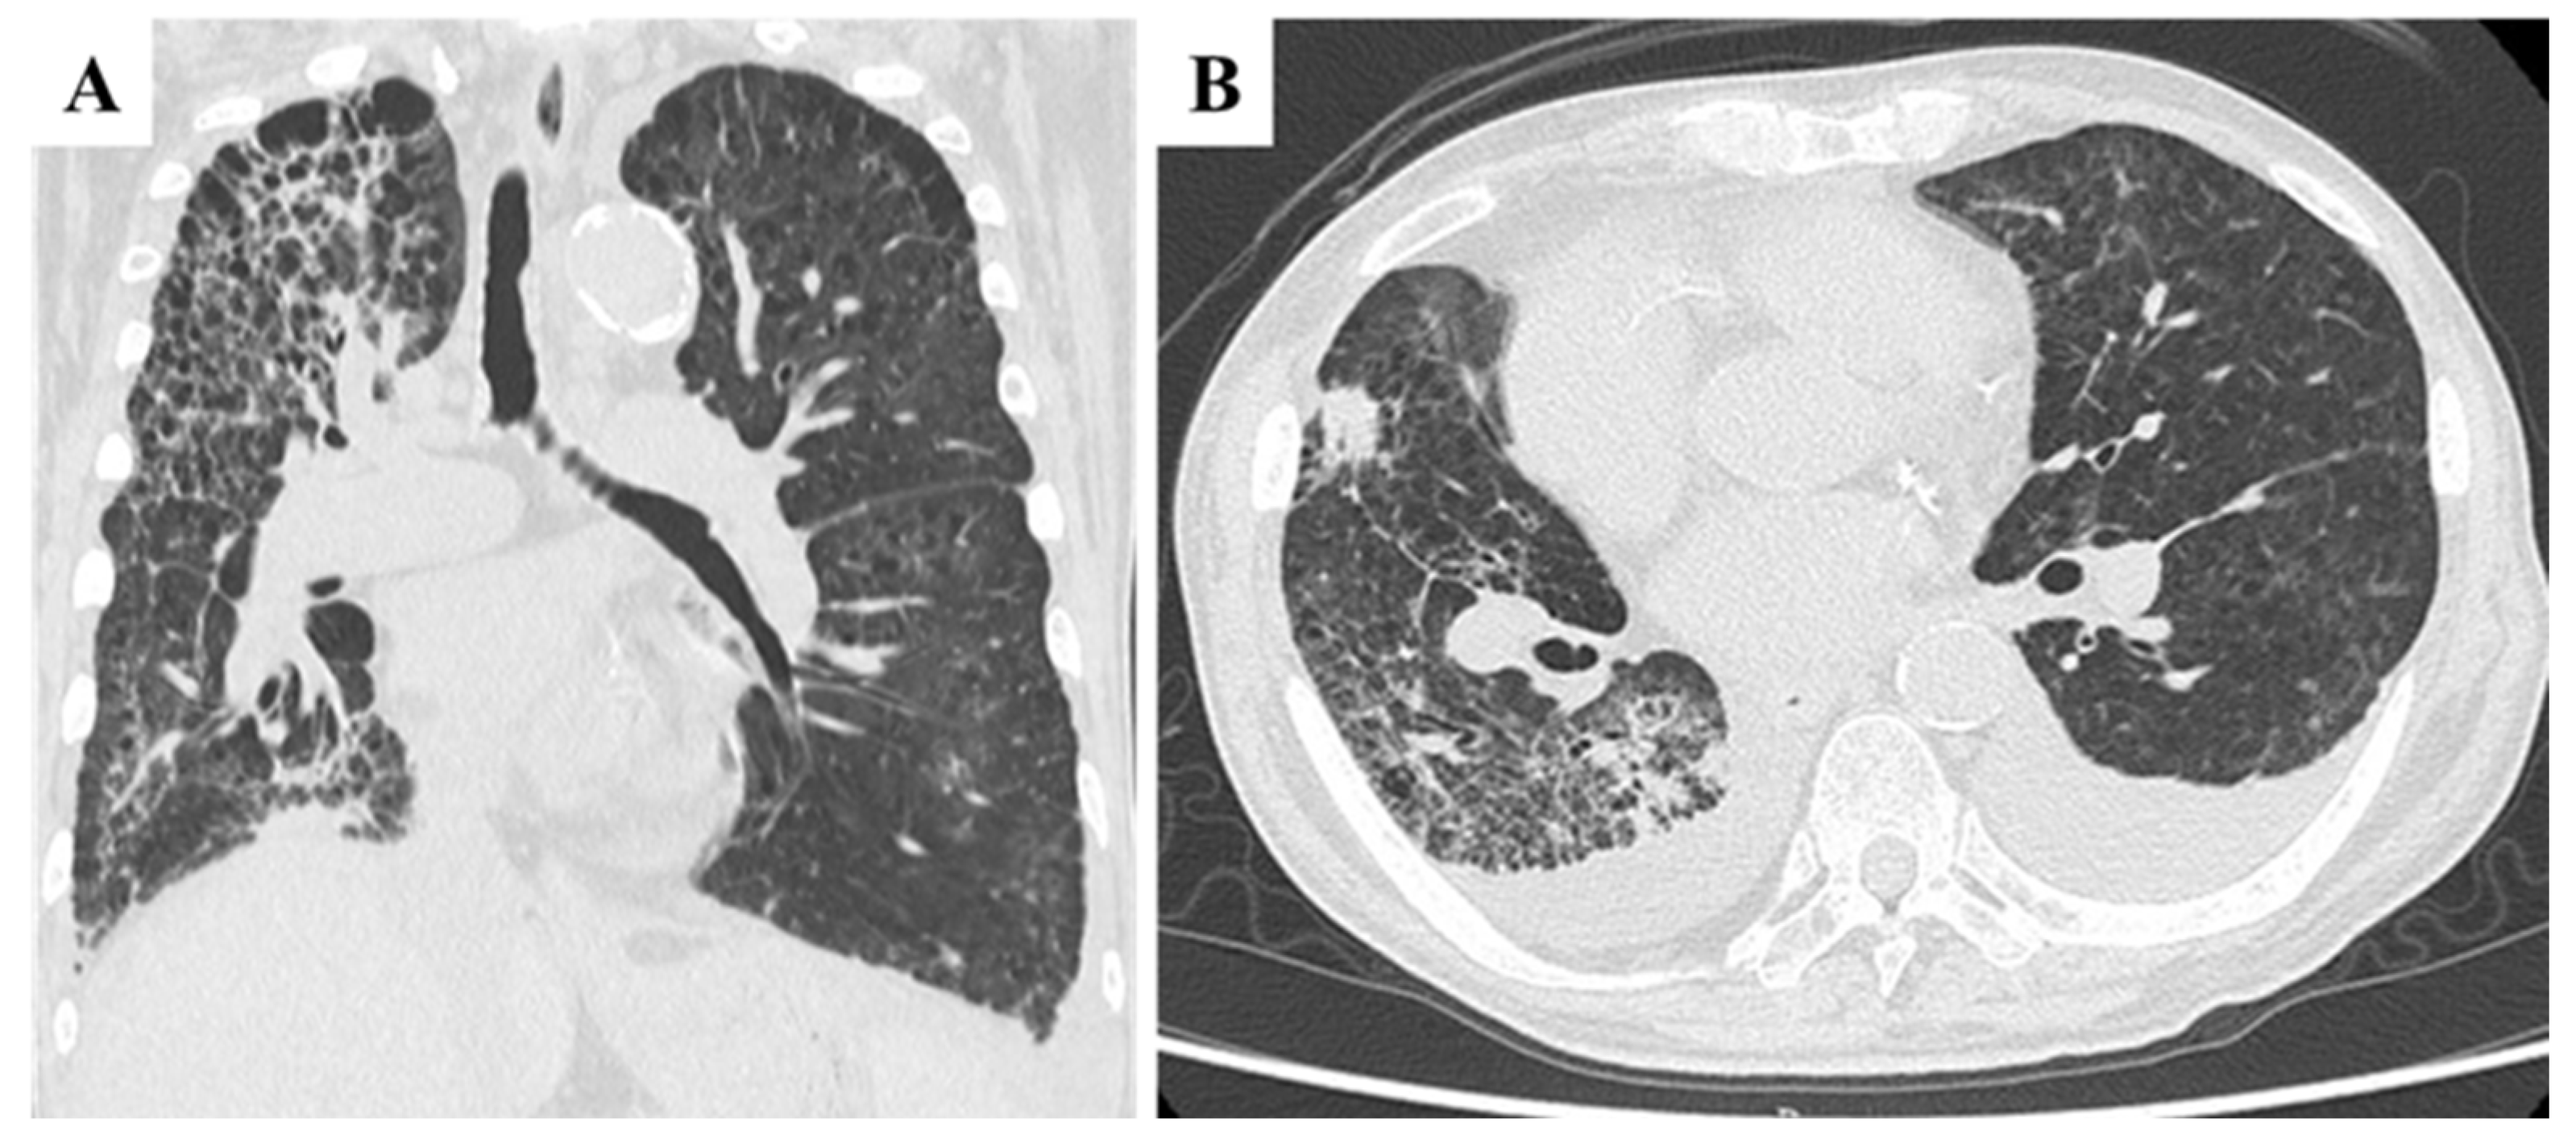

A 70-year-old Japanese male with a history of smoking and alcohol consumption underwent an annual health check-up, during which a fecal occult blood test returned positive for the first time. Subsequent investigations led to a diagnosis of transverse colon cancer with peritoneal metastases. Contrast-enhanced computed tomography (CECT) revealed an irregular mass in the transverse colon near the hepatic flexure, along with multiple peritoneal nodules primarily localized to the greater omentum (Figure 1A). Chest CT revealed multiple blebs in both lung apices and a reticular pattern in the right lung (Figure 1B). Despite peritoneal dissemination, no hematogenous or lymphatic metastases were evident at this stage.

Figure 1. Pretreatment findings from abdominal contrast-enhanced CT and chest CT. (A): Coronal section view showing a tumor in the transverse colon near the hepatic flexure (arrow) and a peritoneal metastatic nodule located just caudal to the primary tumor (arrowhead). Several additional peritoneal metastatic nodules were observed along the greater omentum. (B): Chest CT revealed multiple blebs in both lung apices, along with a reticular pattern in the right lung lobes.